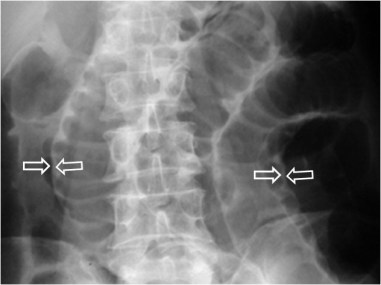

Signo de neumoperitoneo abundante en la radiografía simple de abdomen. El aire alrededor de los ligamentos umbilicales laterales dibuja éstos como dos líneas densas convergentes por arriba, en la zona de la pelvis (flechas).

Reconstrucción coronal en un plano anterior de TC abdominal en un paciente con neumoperitoneo abundante. Podemos ver el ligamento falciforme (flecha blanca), el ligamento teres (flecha roja) y los ligamentos umbilicales anteriores (flechas azules) que forman la V invertida.